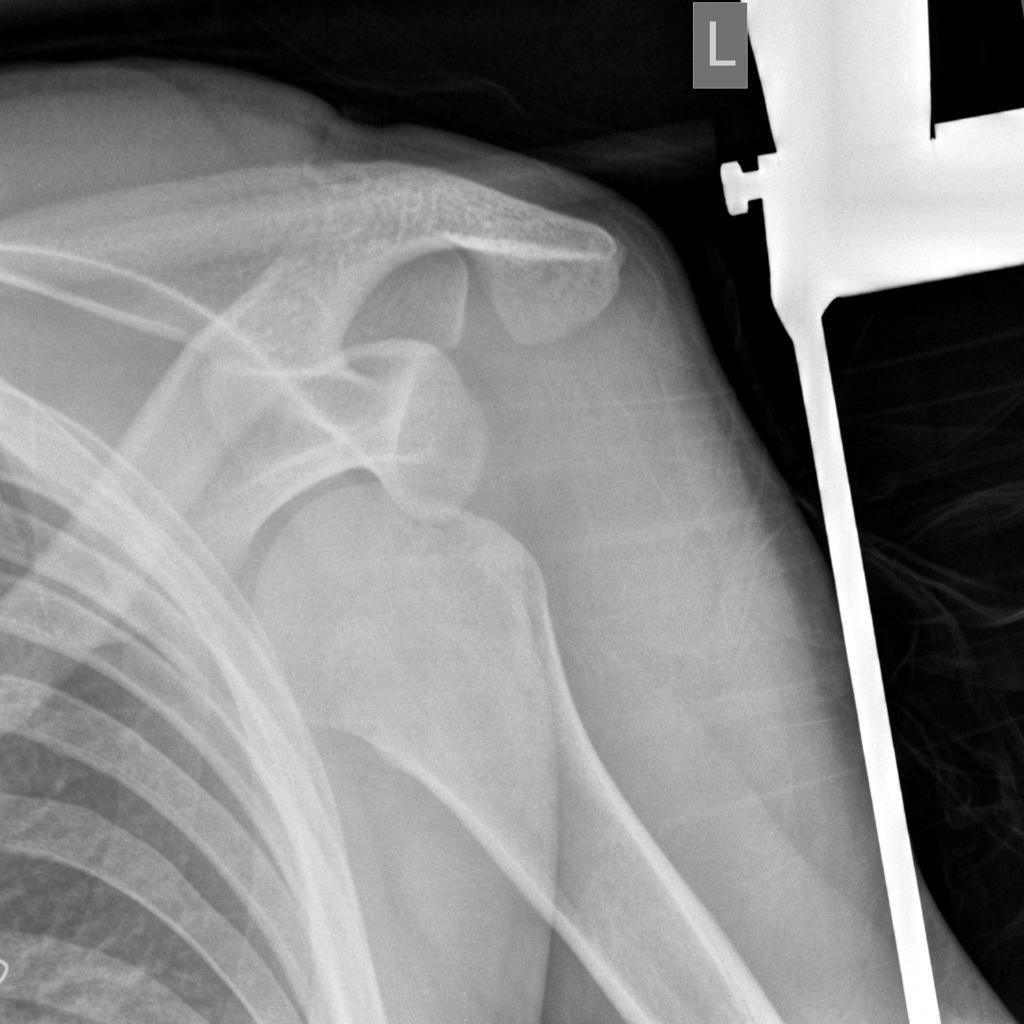

What injury can be seen?

Anterior shoulder dislocation

What nerve injury can be associated with an anterior shoulder dislocation?

Axillary nerve injury